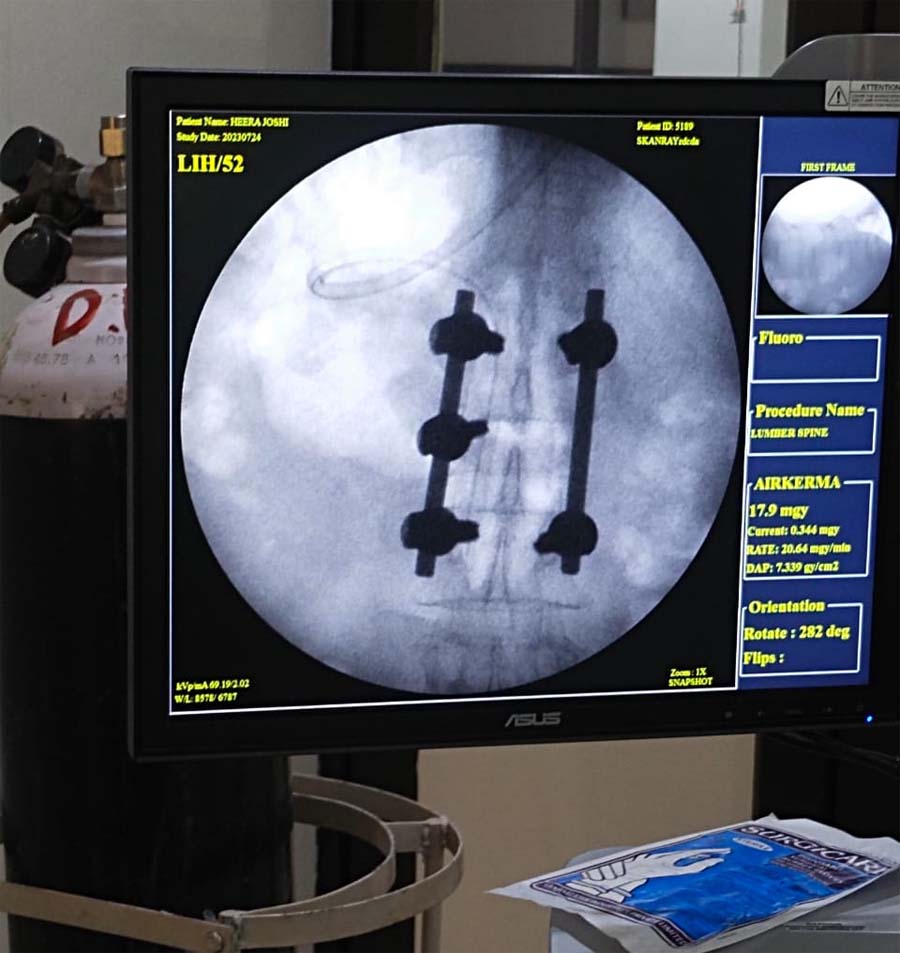

दुर्ग : दुर्ग सिविल सर्जन डॉ. वी. के. शर्मा के नेतृत्व में दुर्ग जिला चिकित्सालय ने एक और उपलब्धि हासिल की है. जिला चिकित्सालय दुर्ग पूरे राज्य में एकमात्र ऐसा अस्पताल है जहां पर न्यूरो सर्जन की पदस्थापना हुई और जीरो रिफरल की रणनीति पर कार्य करते हुए सबसे पहले न्यूरो सर्जरी केस को कर पाने में आज सफलता प्राप्त की. जिला चिकित्सालय दुर्ग में हीरा बाई नाम की 80 वर्षीय महिला का लंबर स्पाइन ऑपरेशन न्यूरो सर्जन डॉ. कुलदीप सिंह एवं निश्चेतना विशेषज्ञ डॉ. बसंत चौरसिया, डॉ. श्रीकांत वर्मा के द्वारा किया गया एवं स्टाफ नर्स शिबेन दानी एवं ड्रेसर रमेश की भी अहम भूमिका रही है.

डॉ. बसंत चौरसिया ने बताया कि महिला घर में ही गिर गई थी जिसके कारण मरीज की रीढ़ की हड्डी में फैक्चर हो गया था जिसके कारण मरीज उठ व बैठ नहीं पा रही थी एवं बहुत ही ज्यादा दर्द में थी. जिला चिकित्सालय दुर्ग में डॉ. कुलदीप सिंह को ओपीडी में चेकअप कराने के पश्चात् उनके द्वारा ऑपरेशन कराने की सलाह दी फिर उनका मेडिकल चेकअप करवाने के बाद मरीज का सफलतापूर्वक ऑपरेशन कराया गया एवं मरीज आज पूर्णतया स्वस्थ है.